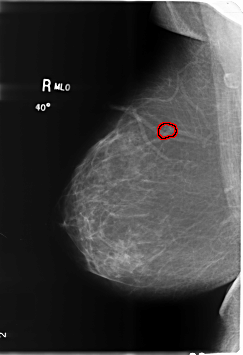

ics_version 1.0 filename B-3486-1 DATE_OF_STUDY 1 6 1998 PATIENT_AGE 39 FILM FILM_TYPE REGULAR DENSITY 1 DATE_DIGITIZED 4 6 1999 DIGITIZER LUMISYS LASER SEQUENCE LEFT_CC LINES 6016 PIXELS_PER_LINE 4128 BITS_PER_PIXEL 12 RESOLUTION 50 NON_OVERLAY LEFT_MLO LINES 6000 PIXELS_PER_LINE 4184 BITS_PER_PIXEL 12 RESOLUTION 50 NON_OVERLAY RIGHT_CC LINES 6024 PIXELS_PER_LINE 4144 BITS_PER_PIXEL 12 RESOLUTION 50 OVERLAY RIGHT_MLO LINES 6024 PIXELS_PER_LINE 4120 BITS_PER_PIXEL 12 RESOLUTION 50 OVERLAY |

FILE: B_3486_1.RIGHT_MLO.OVERLAY TOTAL_ABNORMALITIES 1 ABNORMALITY 1 LESION_TYPE CALCIFICATION TYPE PLEOMORPHIC DISTRIBUTION CLUSTERED ASSESSMENT 4 SUBTLETY 3 PATHOLOGY BENIGN TOTAL_OUTLINES 1 BOUNDARY |